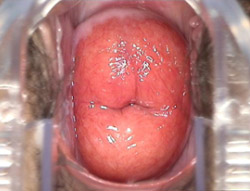

重度宫颈糜烂症状的图片

轻度、中度、重度宫颈糜烂症状的图片

重度宫颈糜烂